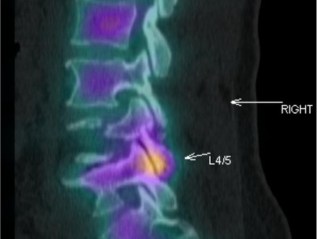

Slipped discs, Sciatica, Nerve root pain and Spinal Stenosis

Mr LHI was recommended to Dr Thomas because I had been experiencing serious back and hip pain, for over twelve months… He gave me a detailed and comprehensible explanation of the causes of my pain, using the MRI scan. He then discussed with me the various treatment options which were available. The staged approach which he considered the most appropriate was both prudent and logical, and ultimately successful. His knowledge, skill and professionalism are self evident and inspires confidence.